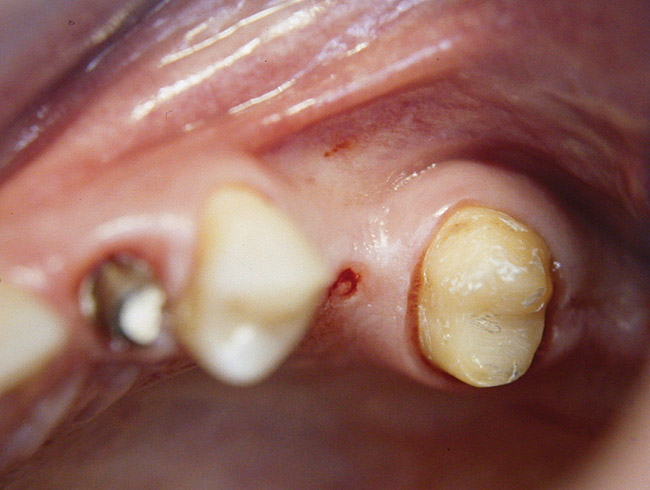

Second-stage surgery was performed after 5 months; healing abutments were placed, and the soft tissue was allowed to heal for an additional 5 weeks. Splinted porcelain-fused-to-metal (PFM) crowns supported by custom gold abutments then were delivered (Figure 5).

Figure 5  Final implant-supported PFM restorations.

Figure 5